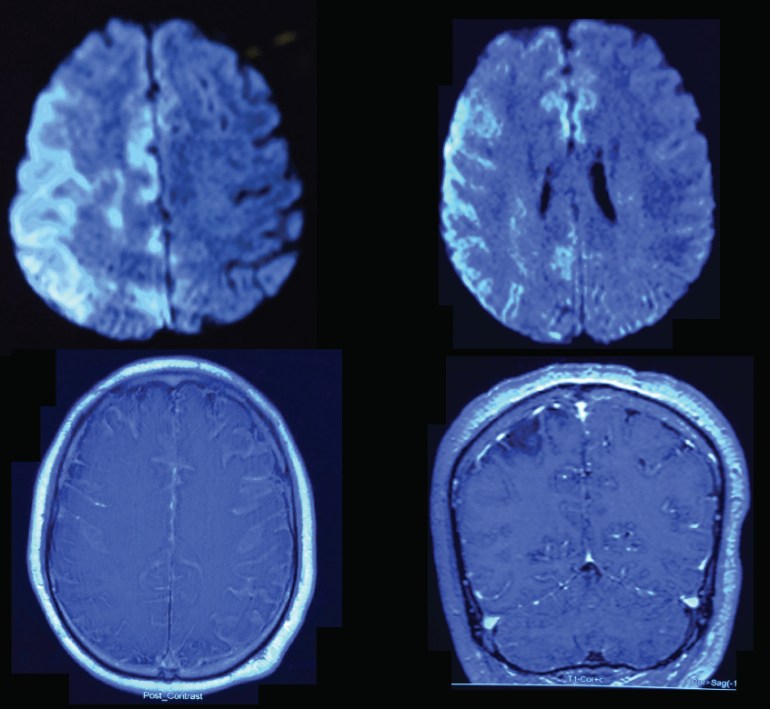

He was treated with high dose intravenous (IV) ceftriaxone and IV ampicillin, as well as IV dexamethasone for presumptive meningitis +/- brain abscess. The relevant MRI images done on the same day are shown below:

[…] The outbreak is technically over, but the publications are starting to appear. Here is a local work describing a subset of 14 patients with GBS brain infections, showing a unique pattern of imaging appearances, just published in the Journal of Magnetic Resonance Imaging (alas behind a paywall). I had previously shown the MRI images of a man with ST283 GBS meningo-encephalitis as a clinical vignette. […]